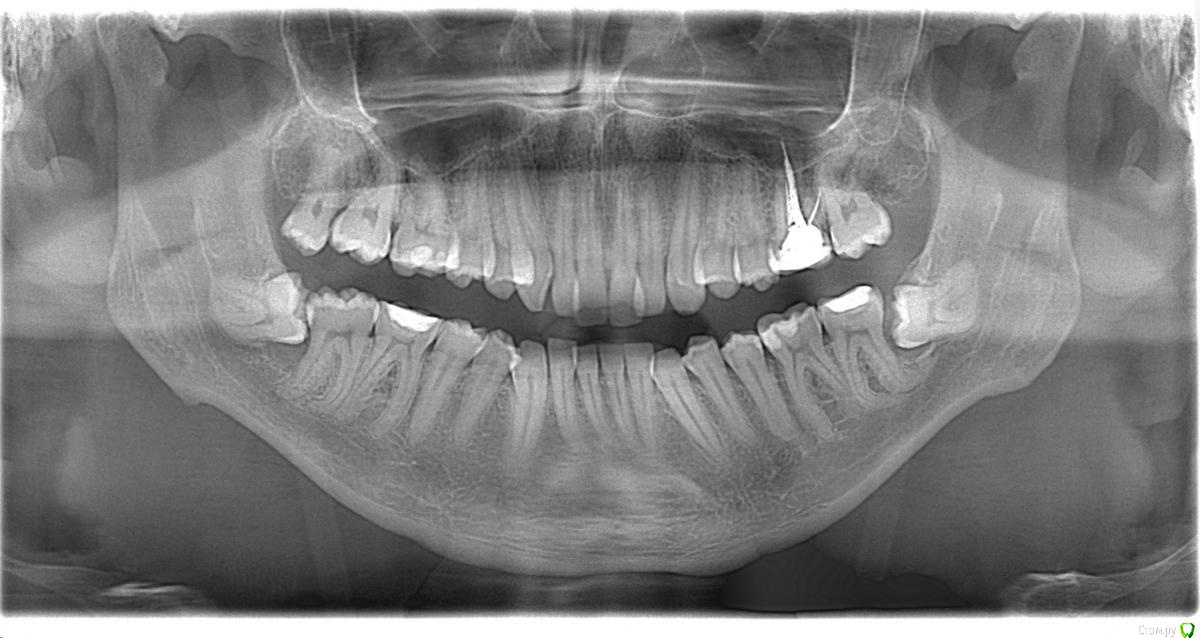

Здравствуйте, Коллеги. Вот такой вот случай, пациент 32 года. Изначально, хотел дистализировать в первом сегменте с целью апрайтинга 13 - 16, провести апрайтинг боковых зубов н/ч, затем САРПЕ и MEAW, понятно, что восьмерки долой еще до лечения. Но потом увидел форму корней 37, 47 (это не искажение, по КТ они и правда такие) и кисты прорезывания за ними. В связи с этим мне кажется, что апрайтинг снизу невозможен, так как эти верхушки никуда меня не пустят, разве что ввиду проблем с пародонтом семерки тоже уйдут. Вопрос: что делать??? Даже если отбросить мультилуп и готовить его на ортогнатию, то апрайт все-равно нужен, как поступить? Заранее спасибо!

P.S.: Забыл... сверху семерки такие же.